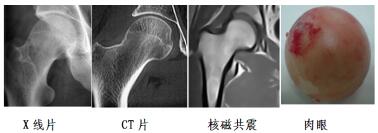

壞死股骨頭

股骨頭(連接大腿和臀部的一個關節(jié))壞死全稱股骨頭缺血性壞死,是一種由股骨(即大腿骨)血供中斷或受損,引起骨細胞和骨髓成份死亡及隨后的修復,繼而導致骨頭結構改變,股骨頭塌陷,從而引發(fā)關節(jié)功能發(fā)生障礙的疾病。